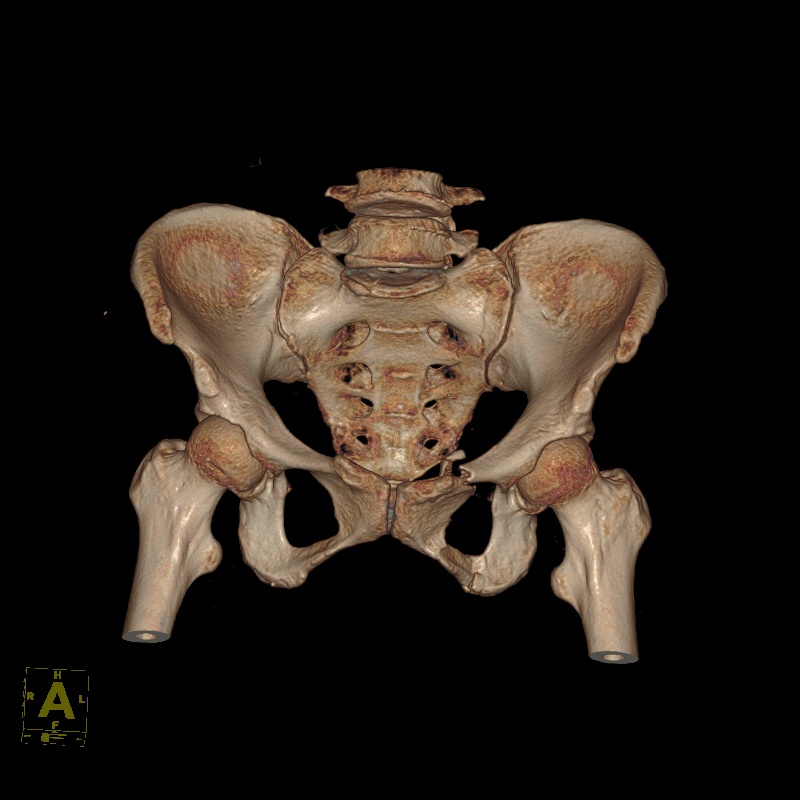

创伤骨科以中西医结合诊治四肢骨关节创伤为主要临床任务和研究方向。为患者提供最恰当的治疗方案和方法。应用传统的闭合手法复位小夹板固定技术、中西医结合内、外固定技术和现代生物学固定理念微创技术治疗四肢、骨盆及关节的各类新鲜、陈旧的复杂难治性骨折。注重中医中药三期辨证施治(内服外用)在骨折治疗中的应用。目前,我科在陈旧性骨盆骨折、髋臼骨折属省内领先,使用Ilizarow技术及外固定支架治疗开放性骨折,慢性骨髓炎、骨折不愈合,创伤引起的肢体畸形,在软组织修复方面有独特经验。近年来,我科在省内率先开展了系列微创手术治疗各种骨折,尤其是老年髋部骨折(PFNA),使用该方法后,术后1周可扶拐行走,明显减少了各种长期卧床并发症,提高了生活质量,取得了良好的社会效益。

2.骨盆骨折及髋臼骨折

5.手术治疗陈旧性骨盆骨折